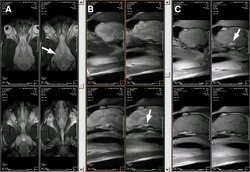

A: SE T1. B: SE T2. C: SE T1 Gd-DTPA |